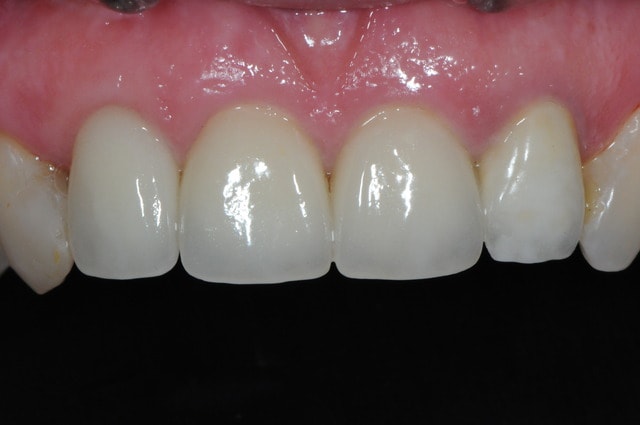

voici - voilà:

photo

1: j+ 2 ou 3 jours

2: j+8 mois

3-4-5: j+ 2 ans

sur la photo 3 on voit à la gencive que l'aspect est moins granité au niveau du col.

c'était ça l'indice pour trouver Charlie.

C'est dommage car ta partie est très bien gérée et au final entre les couronnes dento et implanto portées la luminosité n'est pas la même, est-ce que c'est le même type de couronnes ?

Je me demande si avec Simeda il sera possible de faire des piliers zircone colorés, je pense qu'un peu plus de saturation du pilier n'aurait pas fait de mal, à moins que la couronne soit elle même opaque.

"C'est dommage car ta partie est très bien gérée et au final entre les couronnes dento et implanto portées la luminosité n'est pas la même, est-ce que c'est le même type de couronnes ?

Je me demande si avec Simeda il sera possible de faire des piliers zircone colorés, je pense qu'un peu plus de saturation du pilier n'aurait pas fait de mal, à moins que la couronne soit elle même opaque."

** suis aussi de ton avis, la zircone est trop blanche, j'aimerai des piliers plus suturés

les couronnes sont faites avec une chape zircone